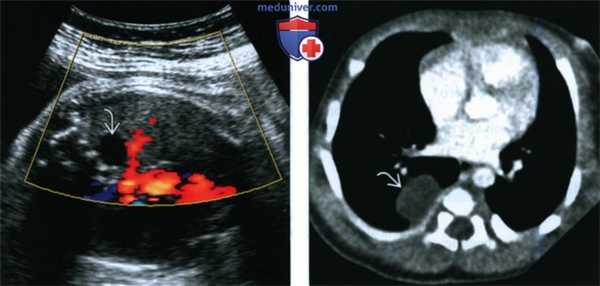

(Слева) Тот же случай. ЦДК, поперечная плоскость. Кровоток внутри кисты не определяется. В связи с близостью расположения к позвоночнику была заподозрена нейроэнтерическая киста, однако аномалии развития спинного мозга выявлены не были.

(Справа) КТ с применением контрастного препарата в аксиальной плоскости, выполненная у новорожденного. Визуализируется простая однокамерная киста. Тело прилежащего позвонка не изменено. Образование иссечено у ребенка в возрасте 6 мес., подтвержден диагноз бронхогенной кисты.